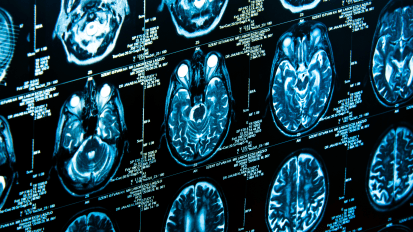

Occult Atrial Fibrillation - Diagnosis and Management

What is the link between AF and stroke patients?